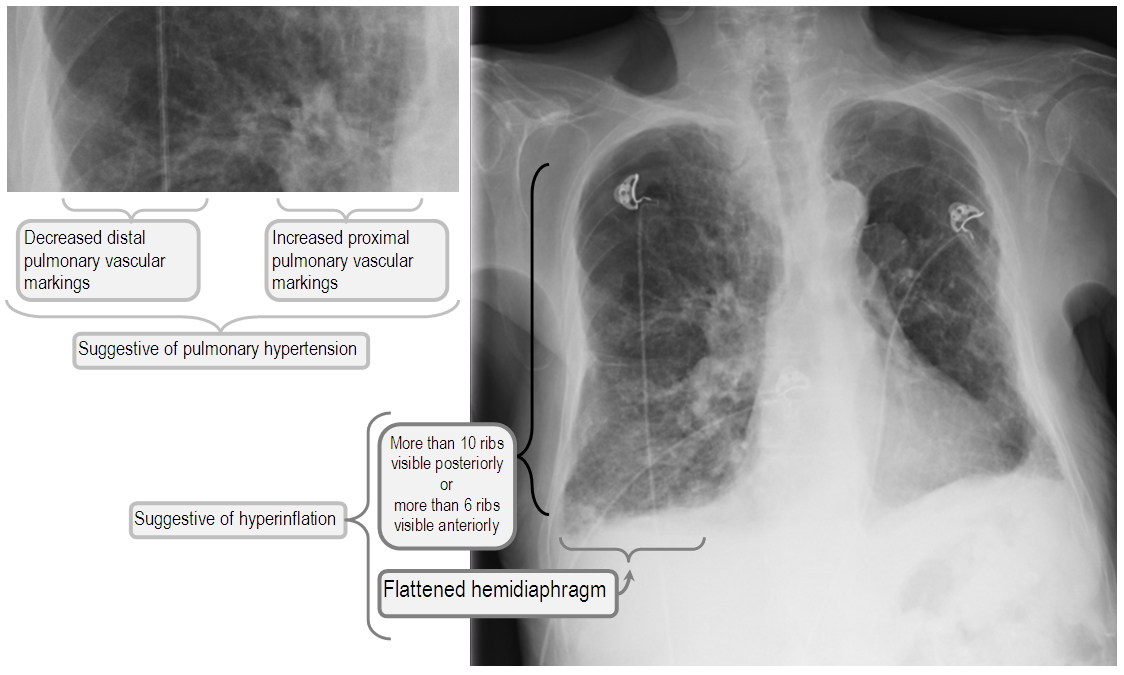

Chest X Ray Copd